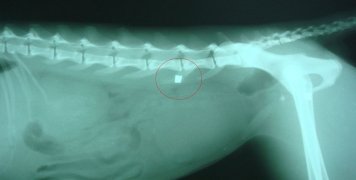

Σύμφωνα μ’αυτήν «το Σάββατο 17 Μαΐου εκτονώνοντας τα βίαια ένστικτά του σε ζώο (αφού φοβόταν να το κάνει σε κάποιο συνάνθρωπό του) γνωστός - άγνωστος πυροβόλησε με αεροβόλο γάτα στη σπονδυλική στήλη. Περαστικός ειδοποίησε το Φιλοζωικό Σύλλογο που περισυνέλλεξε τη γάτα και τη μετέφερε σε κτηνιατρείο. Η σφαίρα αφαιρέθηκε από τον κτηνίατρο Βαλάντη Μάντικα. Παρακαλούμε όποιος γνωρίζει το δράστη ας επικοινωνήσει με το Αστυνομικό Τμήμα Χίου.

Στις φωτογραφίες η γάτα στο ιατρείο και ακτινογραφία της όπου εντοπίζεται η θέση της σφαίρας.»